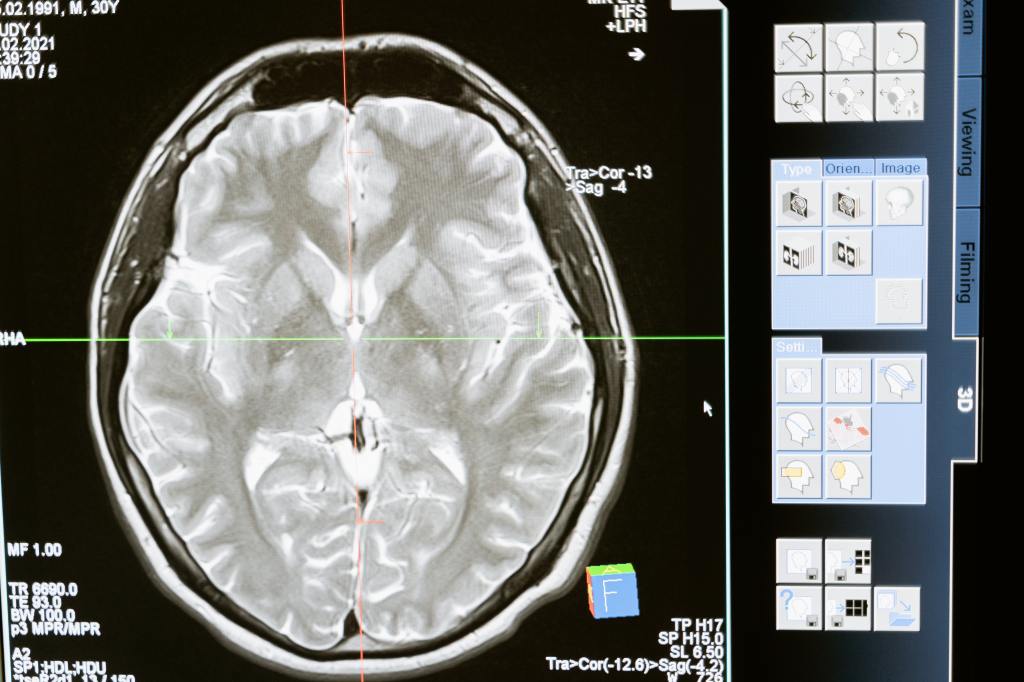

Cada vez que al ser humano se le presenta un problema, es natural que intente buscar la causa y sus posibles consecuencias. A priori, el sustrato de una adicción a la droga parece pertenecer al ámbito de la neurología y la psicología, con lo que, ante un problema de adicción, lo usual es intentar comprender qué estructuras cerebrales han podido favorecer su aparición y, por otro lado, ser modificadas por el consumo prolongado de la droga y si esto es reversible, y qué componentes de mi psicología han podido favorecer el desarrollo de mi adicción y qué aspectos a este nivel han podido verse afectados con posterioridad. Resumiendo, es conocer si tengo predisposición fisiológica o psicológica a ser adicto, y si sufro cambios a estos niveles por el hecho de haberlo sido durante mucho tiempo.

Este es el motivo por el que un fumador puede defender a capa y espada que «fumar es un placer» por el mero hecho de que hacerlo favorece la liberación de dopamina; que un fumador piense que su adicción es incurable por enterarse que sus neuronas tienen mayor número de receptores nicotínicos que un sujeto que nunca ha fumado; o que su caso es irrecuperable por haber sufrido un trauma en la infancia…